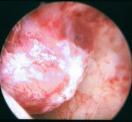

Schließlich ist die Ultraschalluntersuchung auch in der Lage, zur frühzeitigen Entdeckung von Krebserkrankungen beizutragen, wie auf dem unteren Beispiel: links wieder das Ultraschallbild (diesmal zwei Aufnahmen in unterschiedlichen Ebenen, die hellen Strukturen sind die verdächtigen Gewebsanteile), rechts die Veränderungen bei der anschließenden Gebärmutterspiegelung: polypöse Strukturen mit Übergang in einen Gebärmutterkörperkrebs.